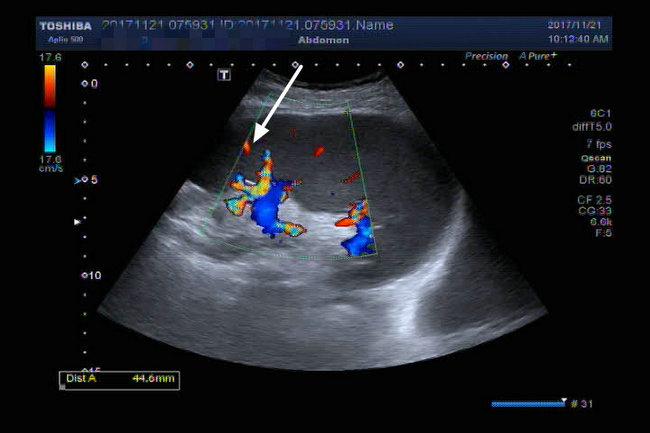

▲ 术前SCT、超声影像检查结果

由于肿瘤较小(1.2*1.4cm),位于左肾肾门处,被血管包围,位置隐蔽,常规超声检查很难发现。超声诊断科主任杨青教授及其精英团队术前反复检查,模拟术中精确定位。术中督导,精确定位,给手术提供动态精准的三D指导,保证了左肾小肿瘤的外科精准切除,术后检查标本肿瘤完整,与术前CT、超声检查符合,术后病理报告:(左)肾透明细胞癌,Fuhrman 1-2级,肿瘤包膜完整,切缘未见癌波及。